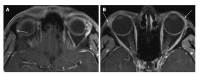

Orbital inflammatory disease (OID) represents a collection of inflammatory conditions affecting the orbit. OID is a diagnosis of exclusion, with the differential diagnosis including infection, systemic inflammatory conditions, and neoplasms, among other conditions. Inflammatory conditions in OID include dacryoadenitis, myositis, cellulitis, optic perineuritis, periscleritis, orbital apicitis, and a focal mass. Sclerosing orbital inflammation is a rare condition with a chronic, indolent course involving dense fibrosis and lymphocytic infiltrate. Previously thought to be along the spectrum of OID, it is now considered a distinct pathologic entity. Imaging plays an important role in elucidating any underlying etiology behind orbital inflammation and is critical for ruling out other conditions prior to a definitive diagnosis of OID. In this review, we will explore the common sites of involvement by OID and discuss differential diagnosis by site and key imaging findings for each condition.